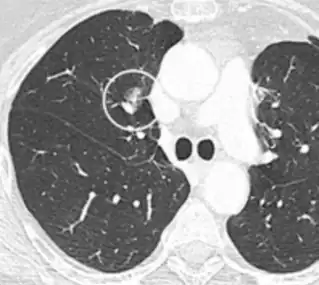

Lobulated nodule.[9]

Spiculated lung nodule.[9]